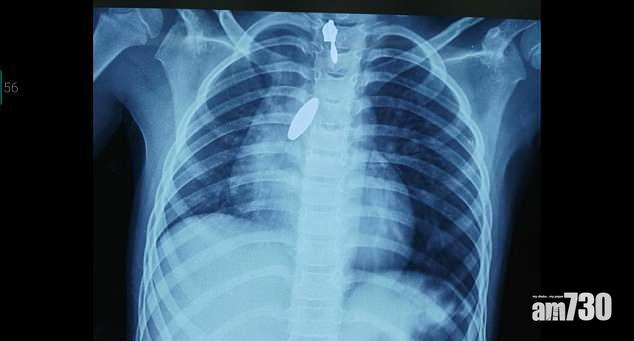

肺卡磁鐵 強力攝石吸出

以毒攻毒,以磁吸磁。印度班加羅爾一名9歲女童玩耍時意外吸入一粒磁鐵,送院救治後,醫生試圖用支氣管鏡檢查儀,夾出附在肺部的1吋長異物,但太滑無法夾穩。最後毋須動手術即將它吸入氣管、再輕易從口而出──妙法是一塊更強的磁石。